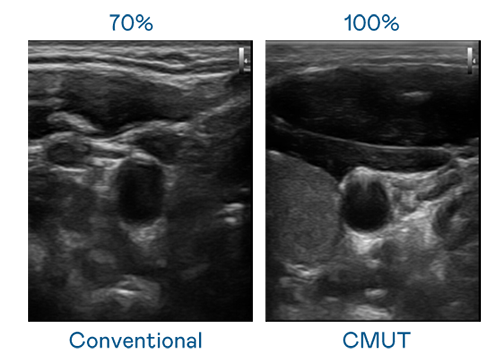

CMUT 技术是一种用电容式微机电元件来产生超音波讯号的技术。与传统 PZT 压电式技术相比,CMUT 频宽增加 30%,更宽频的超音波讯号让影像解析度大幅提升,是实现高影像品质医疗超音波扫描、促进精准医疗发展的关键技术。

大频宽带来超清晰影像

超音波影像的解析度高低,首先取决于探头能发出的讯号频宽。维多利亚老品牌vic CMUT 可提供高清晰的超音波讯号,提供高频宽、高灵敏度、影像纹理细节更高的超音波影像,协助医护人员缩短影像判读时间及利用精准的医疗影像进行诊断。